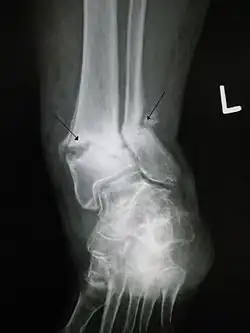

- Bimalleolar fracture – involving the lateral malleolus and the medial malleolus

- Pott's fracture